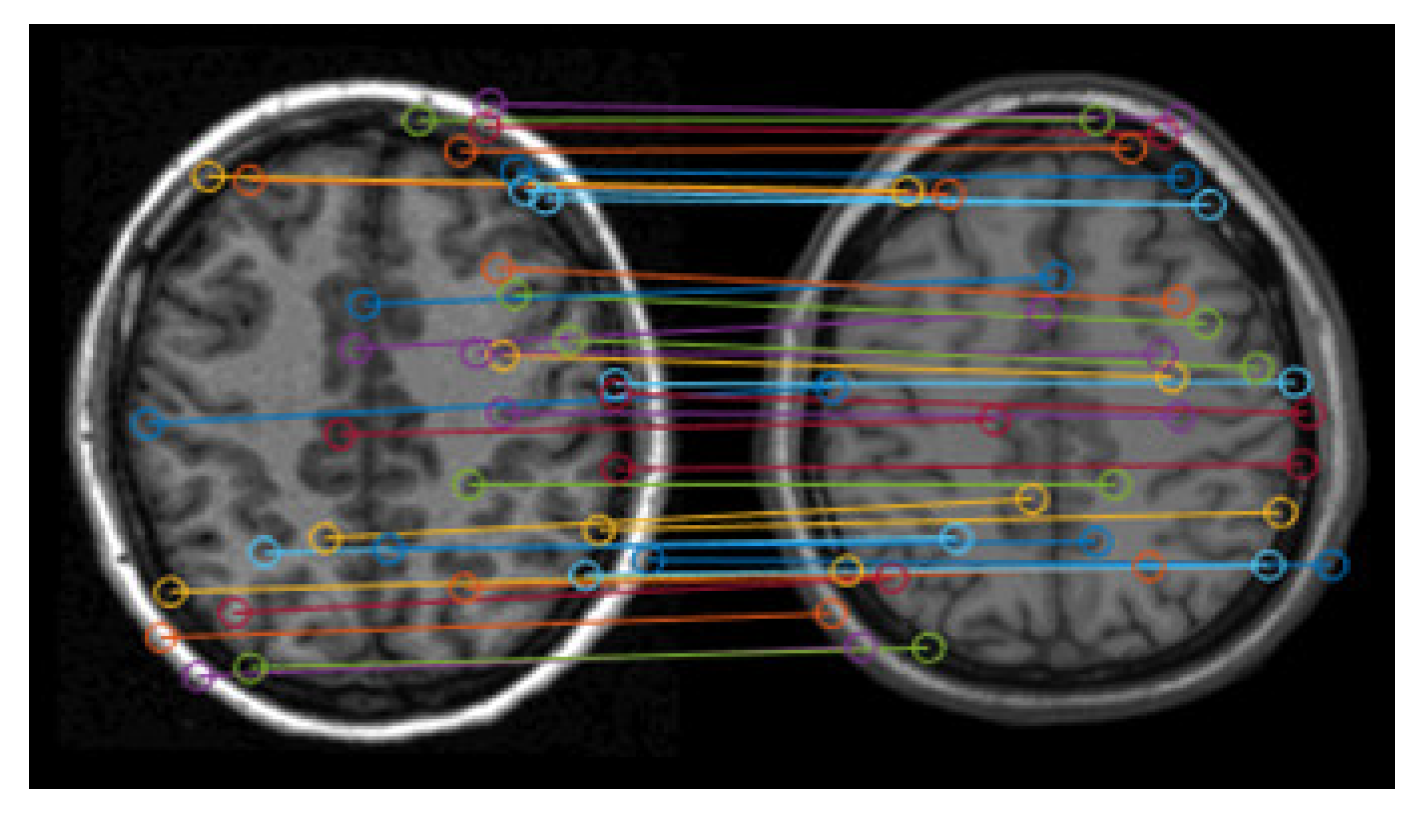

2.1.4. Matching of Feature Points

2.1.5. Screening of Matching Pairs of Feature Points